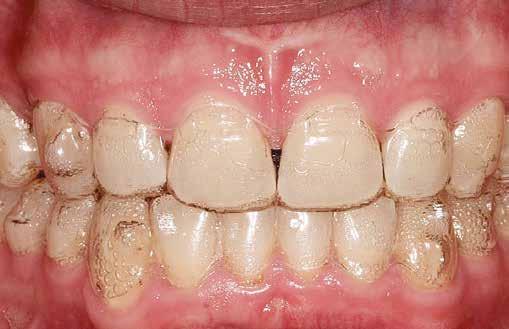

Zachrisson és Mjör [38] 48 eltávolításra kerülő kisőrlőt vizsgáltak. Ezeket a fogakat átalakították, mint a hiányzó fog helyére mezializált szemfogakat. Ezt követően a kisőrlőket értékelték 1 héttel, majd 5 hónappal az elcsiszolás után. Az eredmények szerint amennyiben a csiszoláskor megfelelő a vízhűtés és a módosított felszínek öntisztulókká válnak, akkor ezt a formázást el lehet végezni anélkül, hogy a páciensnek ez kellemetlenséget okozna, továbbá alig vagy nem történik változás a pulpa és dentin területén. A szerzők ugyanezt igazolták a következő tanulmányukban is, ahol 37 kismetszővé átalakított szemfogat vizsgáltak meg 10-17 évvel a csiszolás után [41]. Nem volt szignifikáns különbség a csiszolt és csiszolatlan fogak között a mozgathatóság, kopogtatási vagy hőreakció szempontjából. Pulpaszűkületet találtak, de ennek más oka is lehetett. Mikroszkóp alatt vizsgálva mindössze két fog esetében figyeltek meg a gyémántcsiszolók által hagyott barázdákat és karcolásokat, a többi fog állapota tökéletes volt. Fontos, hogy a zománc elcsiszolásnál figyeljünk a természetes fogformára, elsimított zománcfelszínre (mely biztosítja az öntisztulást) és az elégséges vízhűtésre [38].

Radlanski és mtsai. [54] beszámoltak róla, hogy a perforált korongok 30 µm szélességű és mélységű barázdákat hagynak hátra. Az elcsiszolt felületek extra finom Sof-Lex koronggal történő polírozása után is 10-30 µm mély vájatok maradnak. Ezekben a barázdákban felgyűlhet a plakk, még akkor is, ha a páciens fogselymet használ, és ez növelheti a fogszuvasodás előfordulásának gyakoriságát [55].

Joseph és mtsai [32] szerint az elcsiszolás egyedüli hátránya a nem megfelelő felületi kidolgozás és polírozás. Amennyiben a zománcfelszín viszonylag sima a csiszolást követően, úgy nincs plakk felhalmozódás, és a zomán remineralizálódhat. Zachrisson bebizonyította, hogy az elcsiszolást követően azokon a területeken, ahol a plakk felgyűlhet, megnövekedik